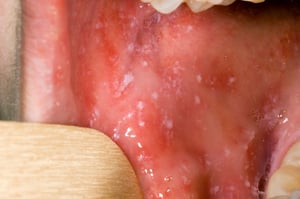

До начала сыпи во рту могут появиться пятна Коплика. Пятна Коплика — это мелкие ярко-красные пятна с белым или синеватым центром. Центр пятна может быть похож на песчинку.

Пятна Коплика — это ярко-красные пятна с белым или синеватым центром, которые могут быть похожи на песчинки. Они могут возникать в любом месте рта у людей с корью.

Изображение любезно предоставлено библиотекой изображений общественного здравоохранения центров по контролю и профилактике заболеваний Public Health Image Library of the Centers for Disease Control and Prevention).